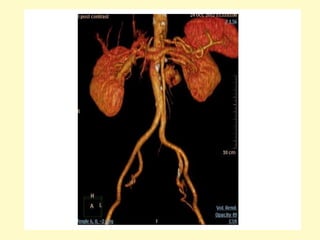

Horseshoe kidney with anteriorly oriented renal pelvis, axial contrast-

enhanced MDCT image (a) shows a horseshoe, the renal isthmus is

found anterior to the great retroperitoneal vessels, corresponding

volume rendering (b) better show the inferior renal isthmus, the

normal renal arteries, and the anterior location of the renal pelvises

I = isthmus, IMA (arrow)

• 23.

Horseshoe kidney withanteriorly oriented renal pelvis, axial contrast- enhanced MDCT image (a) shows a horseshoe, the renal isthmus is found anterior to the great retroperitoneal vessels, corresponding volume rendering (b) better show the inferior renal isthmus, the normal renal arteries, and the anterior location of the renal pelvises

• 25.

I = isthmus,IMA (arrow)